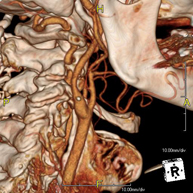

- Angio-TC-Troncos Supraaórticos

Prueba radiológica que consiste en obtener imágenes de las arterias carótidas del cuello de alta definición anatómica mediante el empleo de un equipo de TC (Tomografía Computarizada) y la inyección de contraste intravenoso. Posteriormente, las imágenes son reconstruidas en tres dimensiones (3D). Indicaciones: accidente vascular cerebral agudo, accidente vascular transitorio, soplo carotídeo. - Angio TC- aorta toràcica